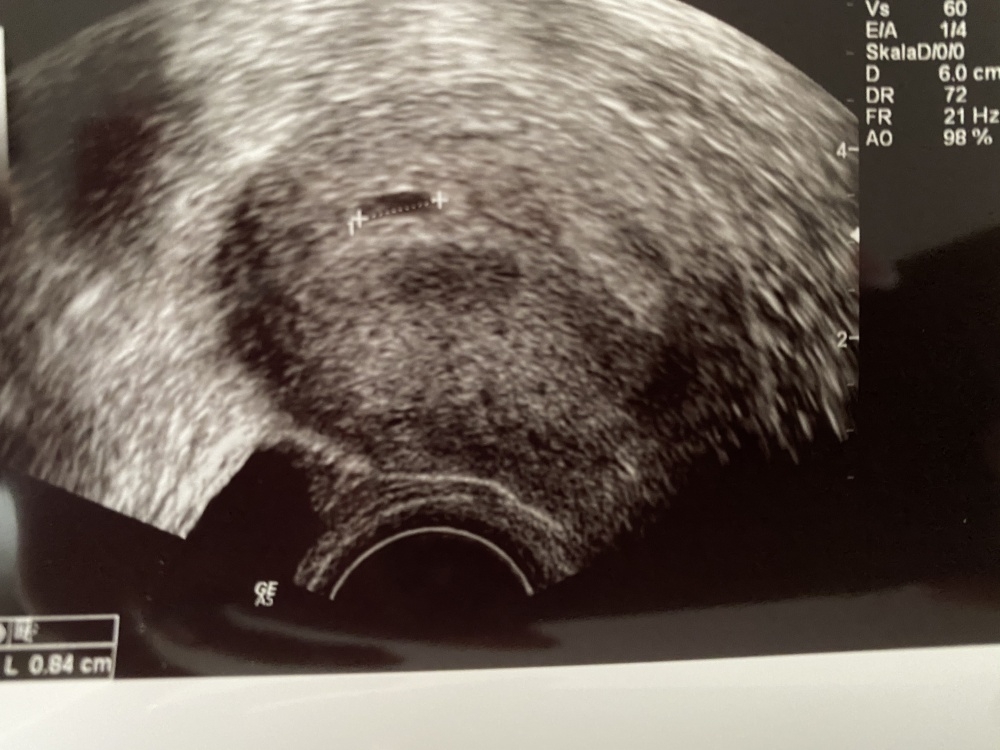

• Hallo, ich war heute beim Frauenarzt und bin laut ihr in der ssw 5+6 die fruchthöhle ist leer und 0,83 cm sie meinte die ist zu klein.. und ich könnte in den nächsten paar Tagen eine Blutung haben und ich soll nächste Woche nochmal zu ihr..

ich habe jetzt total Angst, dass ich mein Kind verliere.. Könnte Sie recht haben oder soll ich einfach abwarten. Bin zum ersten mal schwanger und die Ärztin war Eiskalt hat mir einfach alles gesagt.. Sie meinte das ist ungewöhnlich..0o2qlkqev7r6.jpeg